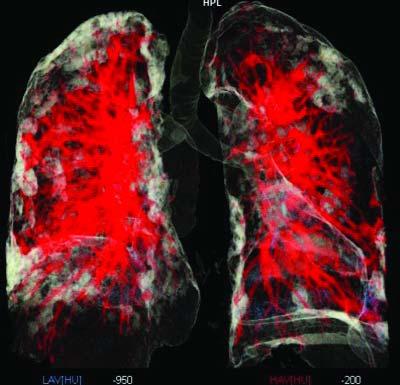

(Image 03) CORONALIMAGE SHOWING THE LESION DISTRIBUTION (Image 04) PULMO 3D Image SHOWING LESIONS (WHITE) SURROUNDING THE BLOOD VESSELS(RED) (Image 05) PULMO 3D IMAGE OFBRONCHIALTREE (MULTICOLOR) AND THE LESIONS (WHITE) RELATIONSHIP

(All the belowimages are acquired on Siemens Healthineers CT,SOMATOM go.Top and processed on Siemens Advanced modality Workstation syngo.via)